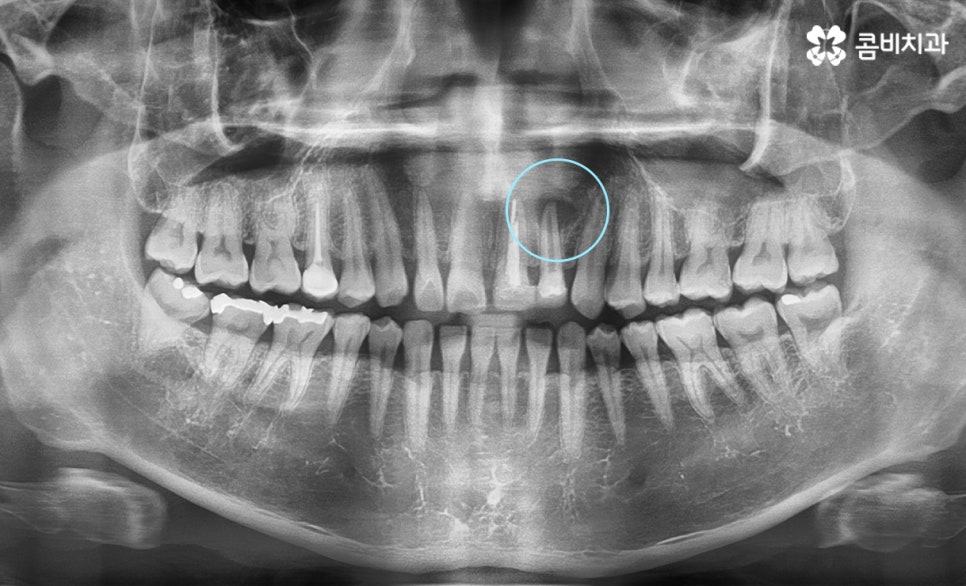

위 엑스레이 사진의 경우 앞니 신경치료 전 상태이며 염증이

치아 뿌리 끝 쪽에 발생하여 신경치료가 필요한 상황입니다.